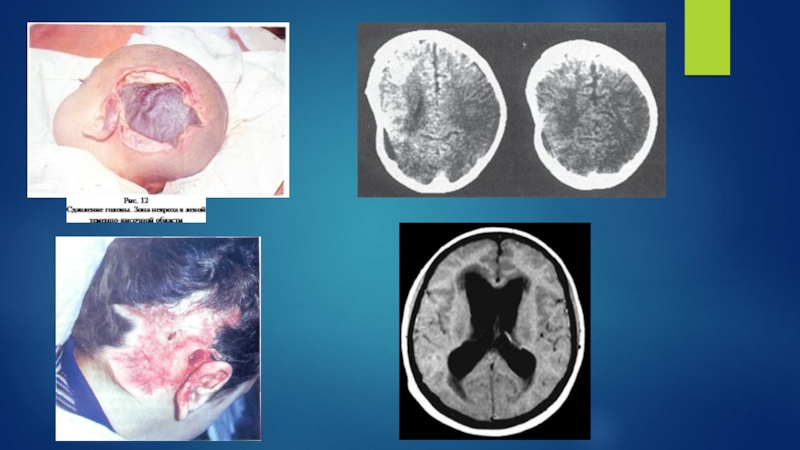

Слайд 9Бас миының ұзақ уақыт қысылуының клиникалық көрінісі БМЖ мен ұзақ

уақыт қысылу синдромдарының ауырлығына, басты қысу бағытына-фронталды және латералды,байланысты болады.

Диагностиканың басты құралы бастың КТ болып табылады. КТ көмегімен бас ми жарақатының ауырлығын, сүйек сынығының түрін, жұмсақ тіндер ісігінің жағдайын айқындауға мүмкіндік береді. Бас ми сүйектерінің сынығы кезінде краниографияның да ролі бар.

Бас миының бір немесе екі жақты қысылуынан зардап шеккендерде, кумбез сүйегінің батыңқы сынығы бар травмадан соң, ісік қайтқан соң бас миының деформациясы болады.